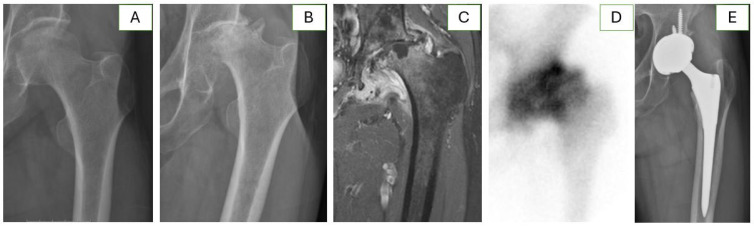

Purpose: Total hip arthroplasty (THA) is the only definitive treatment for rapidly destructive coxarthrosis (RDC). THA for RDC has significantly higher perioperative blood loss with a greater requirement for transfusion than non-RDC primary THAs. Given the rarity of the disease, this study aimed to investigate perioperative and long-term outcomes of cementless THA for RDC that developed from osteonecrosis of the femoral head (ONFH).

Materials and methods: Each of 26 RDC patients was matched to a patient with typical advanced-stage ONFH for comparison, according to age, sex, American Society of Anesthesiologists classification, and the type of implant used. As a primary outcome, perioperative blood loss was calculated as the sum of compensated and uncompensated blood loss.

Results: The RDC group had a significantly larger amount of total perioperative blood loss in comparison to the group with typical ONFH (791.5 mL vs. 511.2 mL, P=0.034), which was primarily attributable to compensated blood loss (496.1 mL vs. 141.5 mL, P=0.024), as uncompensated blood loss was not significantly different (P=0.152). Intraoperative transfusion volume was significantly higher in the RDC group (234.6 mL vs. 46.2 mL, P=0.007), while the difference in postoperative transfusion was marginally significant (P=0.092).

Conclusion: THA for RDC was accompanied by a higher perioperative blood loss, attributable mainly to a significant difference in the amount of intraoperative transfusion, in a matched comparison with patients with typical advanced-stage ONFH. However, extended operation time and prolonged hospitalization along with a large volume of transfusion did not translate into inferior long-term outcomes.